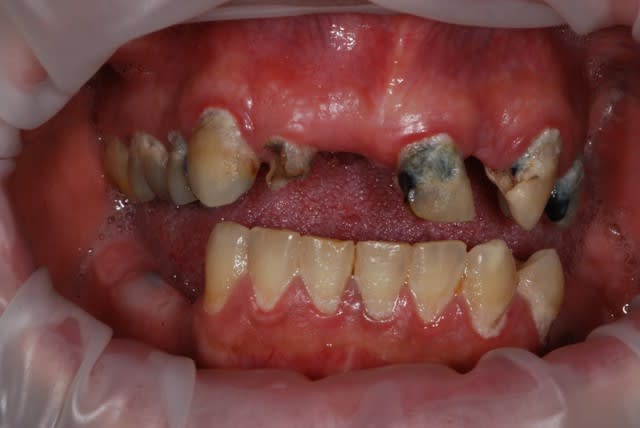

dentiste57

bridge ou contention tartrique ??